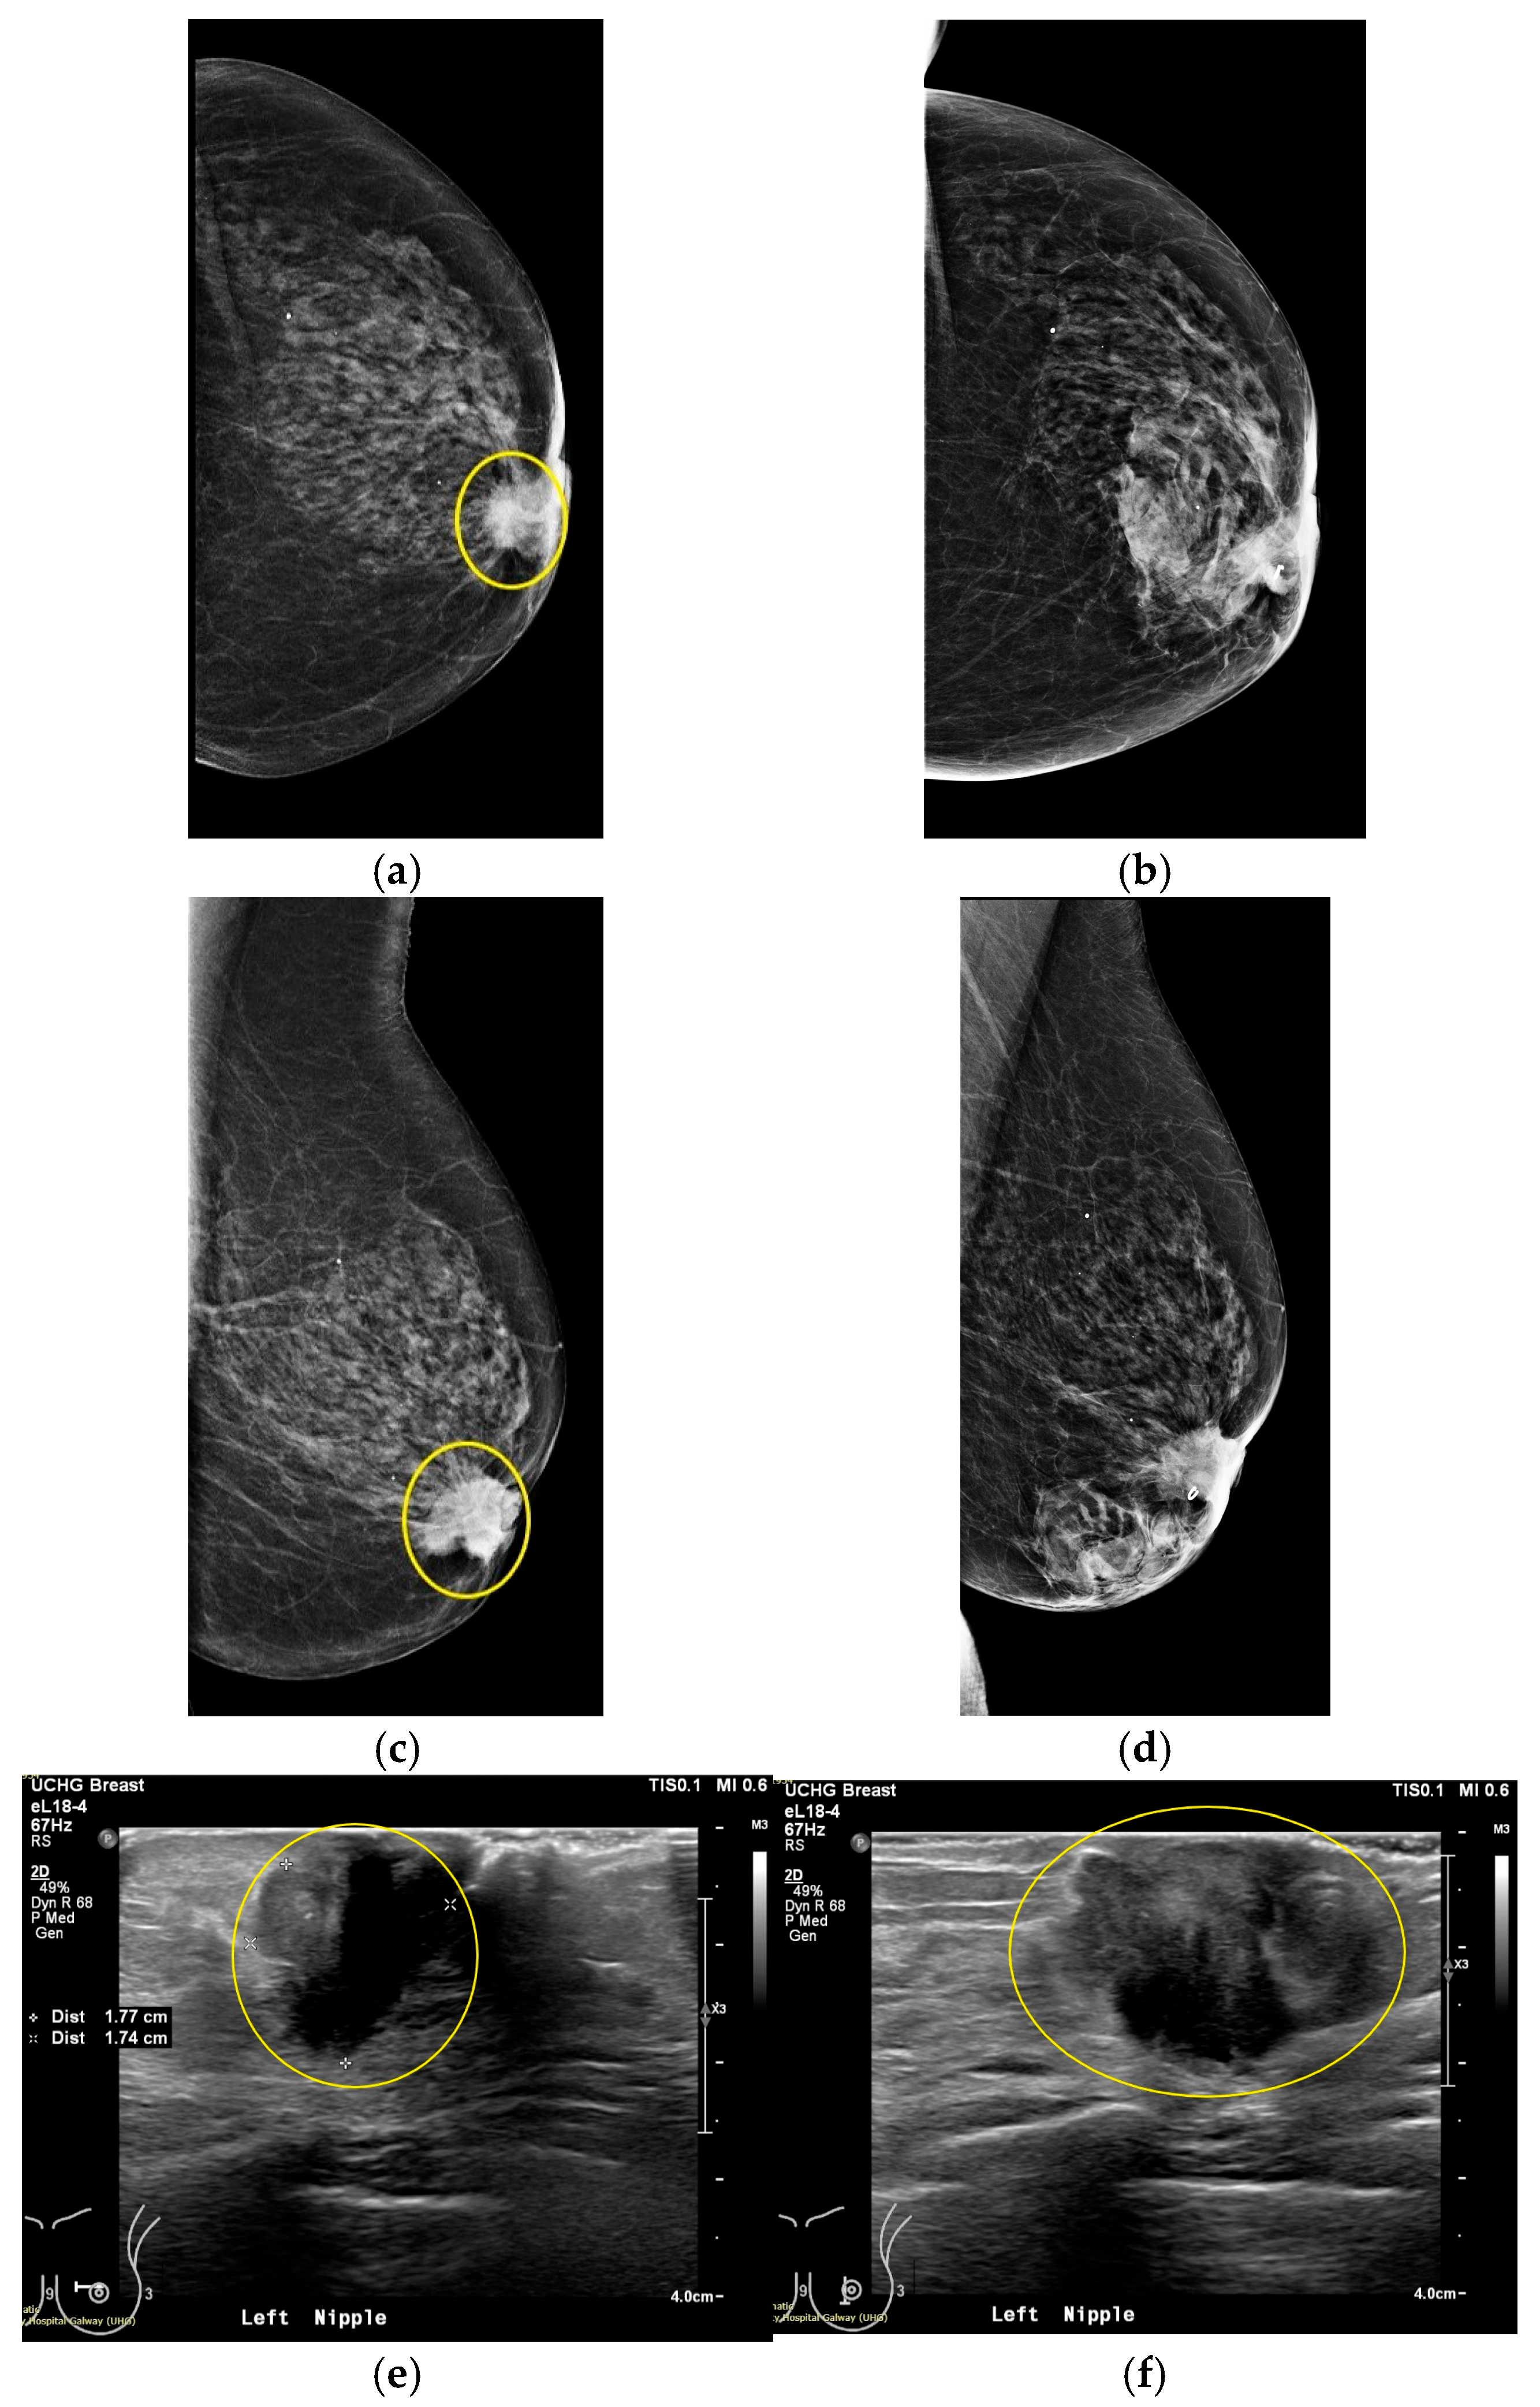

3.1. MWBI Partial Scan of Acceptable Quality and Relevance: Full Example of MWBI Patient Scan Imaging and Image Analysis Outputs for Radiological and Clinical Analysis